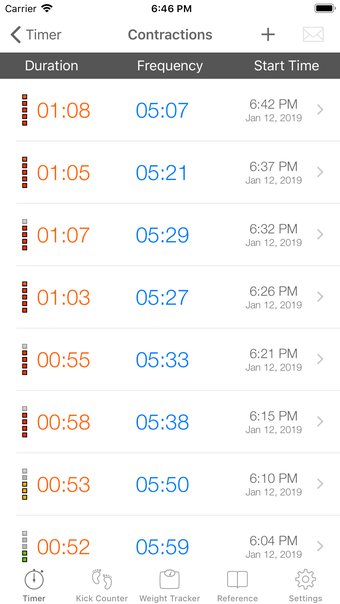

이 어플리케이션은 분만 진행 상황을 명확하게 보여주며, 현재 분만 단계, 이전 및 현재 수축의 시작 및 종료 시간을 보여줍니다. Full Term은 수동으로 각 수축을 시작하고 중지할 필요가 없으며, 어플리케이션을 재시작하더라도 분만 기록을 추적합니다.

수축 옵션 화면에서 어플리케이션이 각 수축 후 자동으로 시작되지 않도록 설정할 수 있는 옵션이 추가되었습니다.